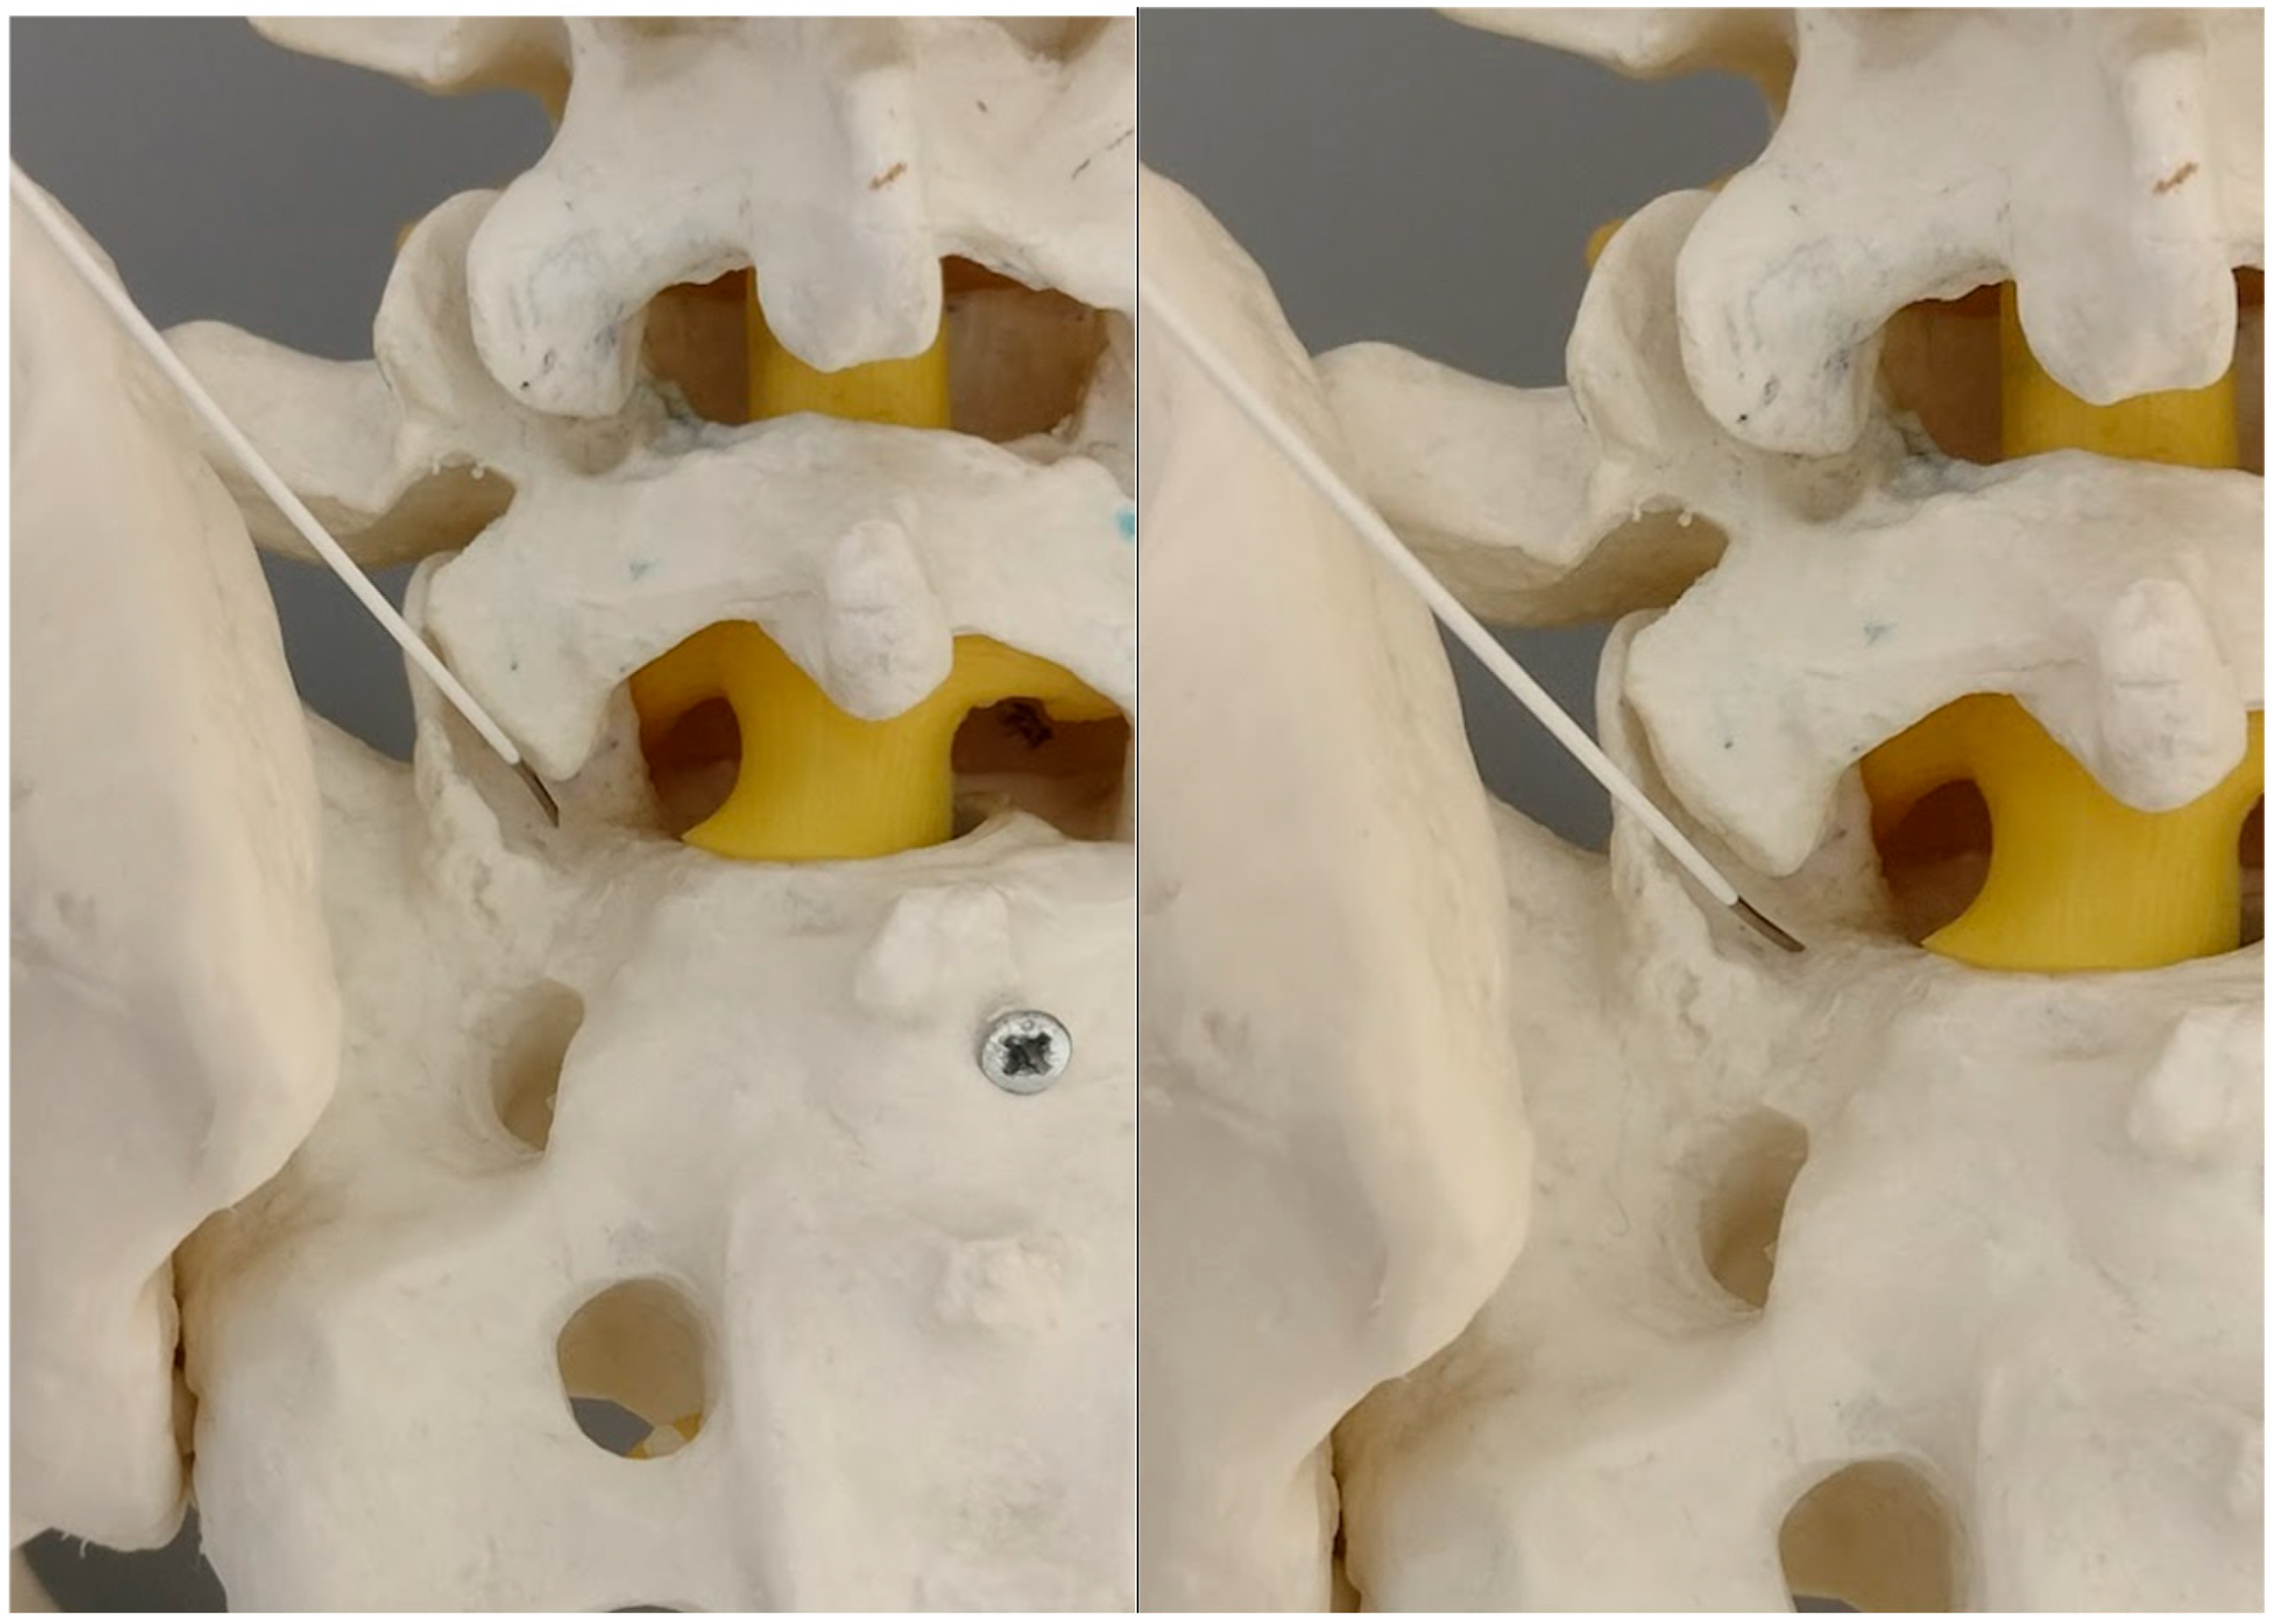

Figure 5. The needle against the inferior part of the S1 facet surface (model). On the right side—twisting the bended tip of the needle points against the medial rim of the S1 facet.

As the needle is placed against the S1 facet it is the secure spot (Figure 4 and Figure 5).

The S1 facet has a cradle-like shape in the transverse plane, so there is no risk of spinal canal violation, as long as it is lateral to the medial border of the S1 inferior facet in the AP view, which is being used from the beginning of the procedure.

The operator can check it by tapping with the tip of the needle toward the midline. There is a sensation of the upward slope; the sudden advancement of the needle with no bone contact necessitates the verification of the needle tip.